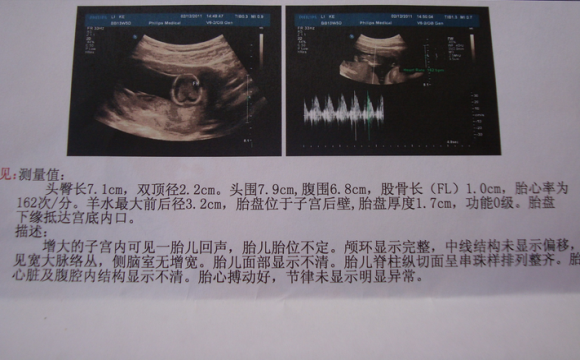

B超是产前检查的一个项目,在怀孕5周的时候可以做一次检查,通过B超了解到妊娠的部位是否正常,排除宫外孕的,也能判断胚胎是否存活。后期的B超能够看出胎儿的发育情况,通过检测的数据算出胎儿的大小等等数据。最重要的是能够看胎儿是否于畸形。

B超能够观察到胎儿的发育生长情况,为早诊断胎儿先天性体表畸形等疾病,提供更加正确的依据。能够及时的发现唇裂,脊椎裂,大脑,肾脏,心脏等等异常情况,这样也能够尽早的进行治疗,提高优生的几率。

检查B超之后,是有一个预测胎儿体重的公式的:胎儿体重(克) = -4973.72 + 260.69*HC(头围)预测胎儿体重公式二 胎儿体重(克) = -2686.60 + 171.48*AC(腹围)预测胎儿体重公式三 胎儿体重(克) = -2232.56 + 747.42*FL(股骨长)。

在这里我们要明确的是,胎儿的体重是看不到的,我们只能根据腹围和宫高来计算胎儿的体重,这只是个大概值,并不代表实际的婴儿体重,预测体重的目的在于及早的发现胎儿发育的问题。一般的,出生时的实际体重会比预测体重有正负10%-15%的误差。这些情况都是正常的。如果宝宝体重越大,误差的范围也就会越大。

胎儿的体重经过B超的检查只是一个大概值,我们还需要通过其他的各种数据搭配才能更加准确的计算出胎儿的体重。